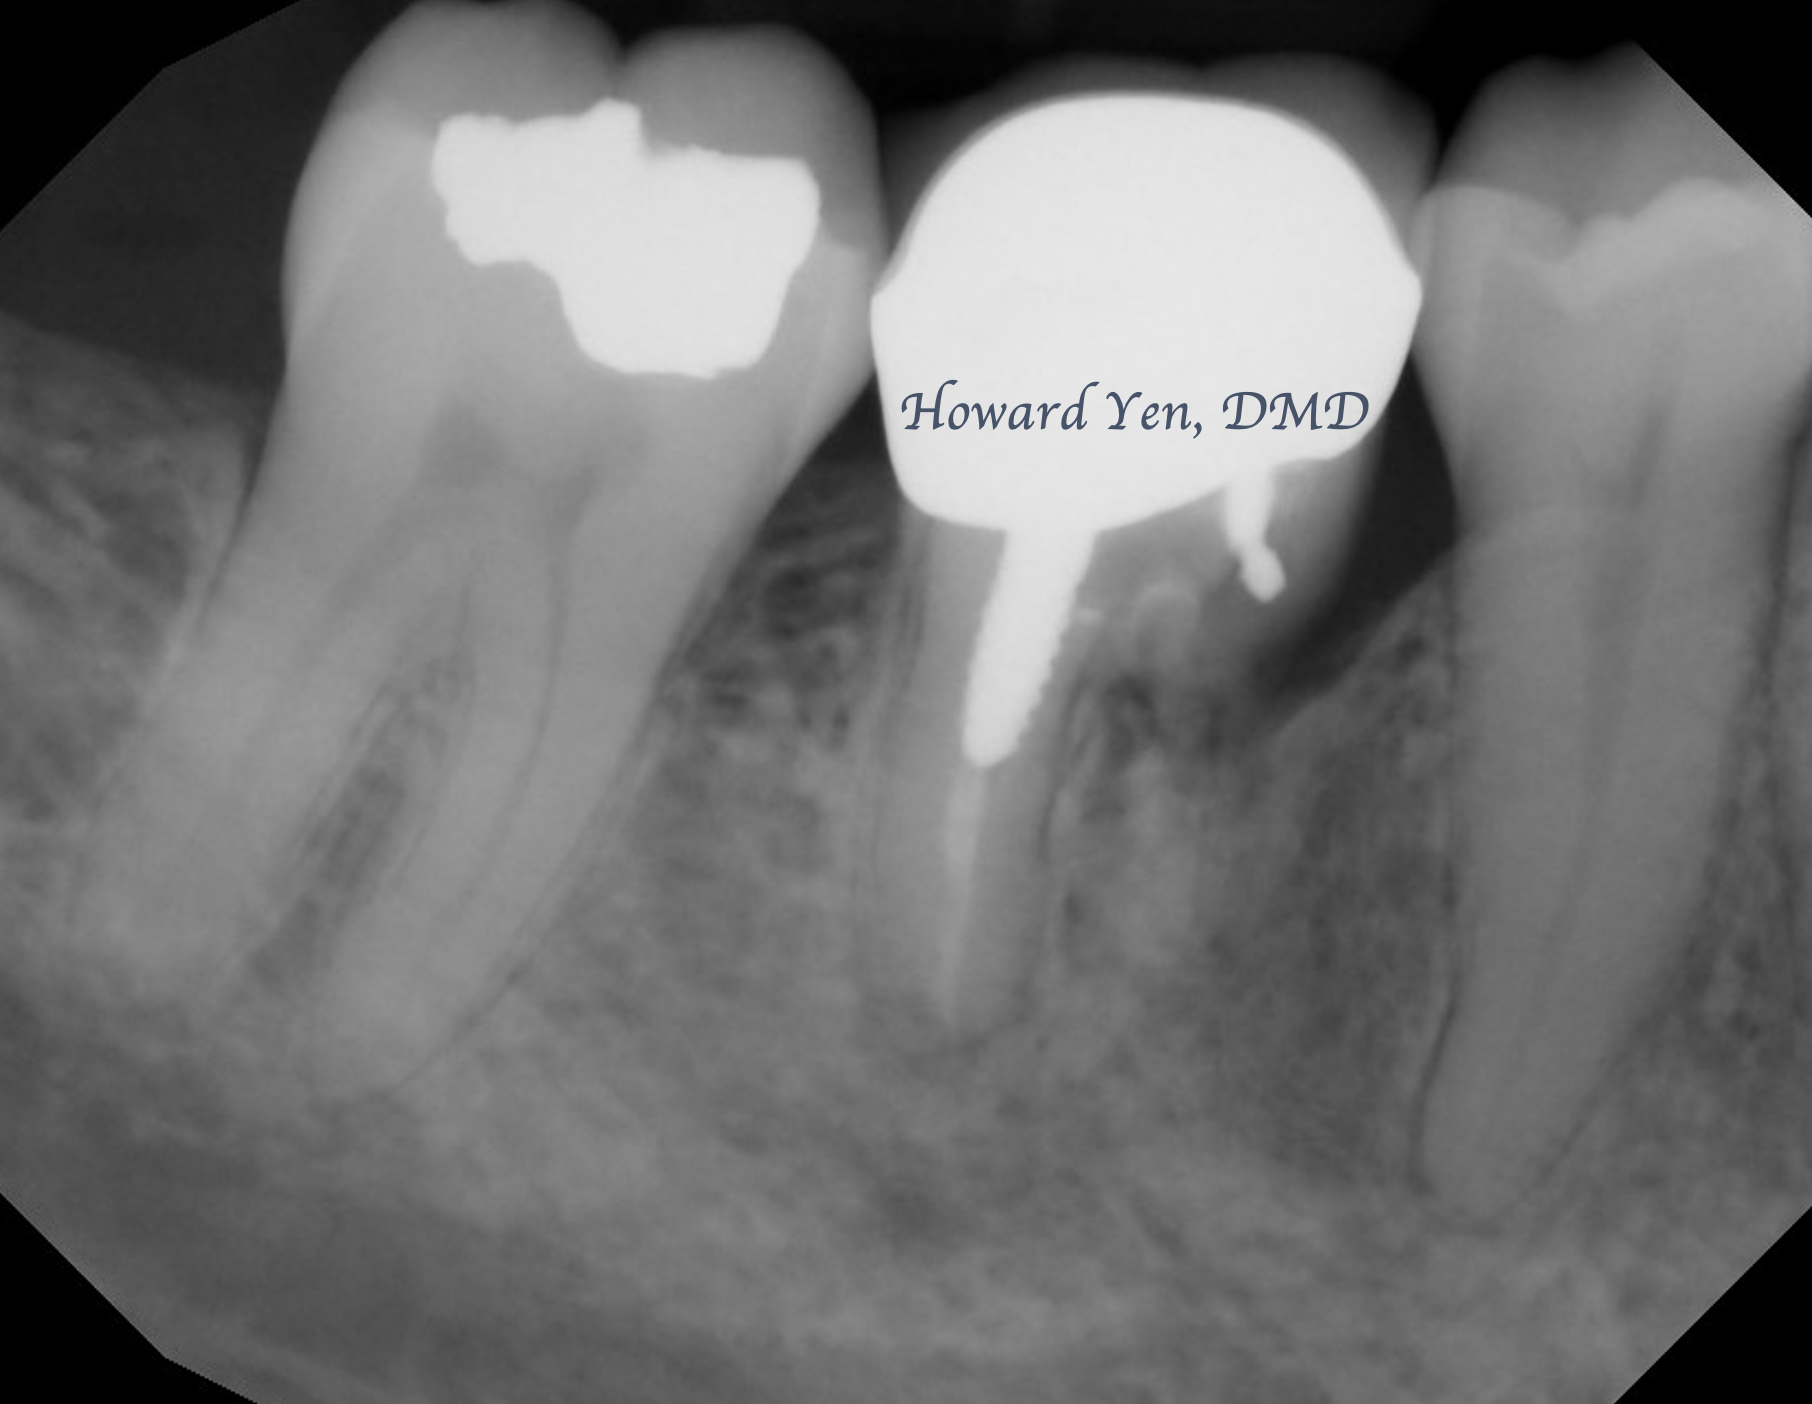

Root Amputation

Root amputation is a surgical procedure to remove diseased/fractured root of a molar in an attempt to further salvage the tooth (crown). The procedure is often done in collaboration with Endodontist (Root Canal Specialist). This is one of the classic conservative treatment option prior to the advent of modern dental implants. With proper case selection, this treatment modality is still an excellent option in preserving natural tooth.